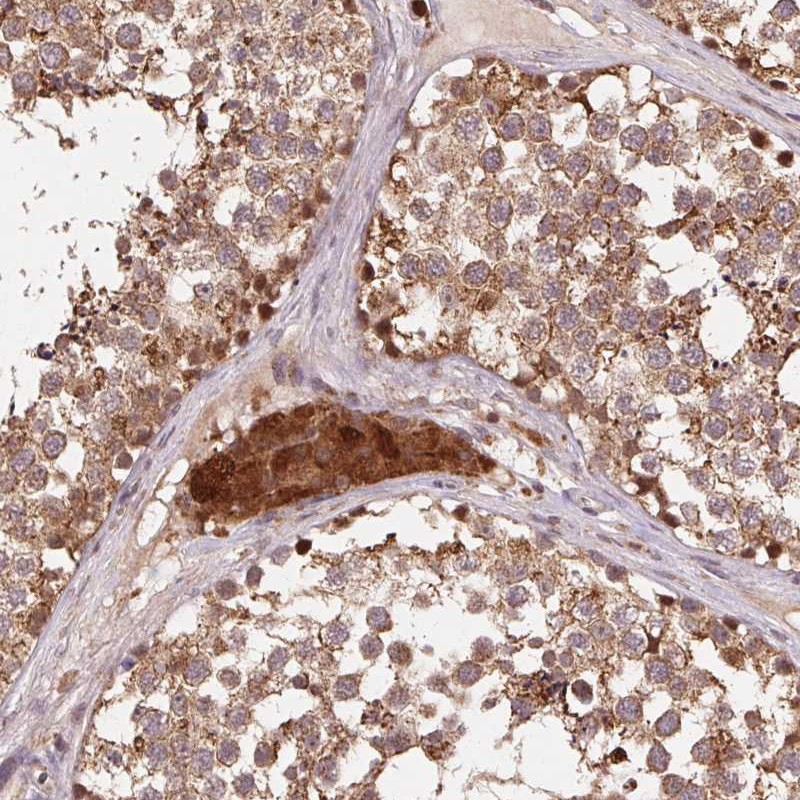

Immunohistochemical staining of human testis shows moderate cytoplasmic positivity in cells in seminiferous ducts, Leydig cells were strongly stained.